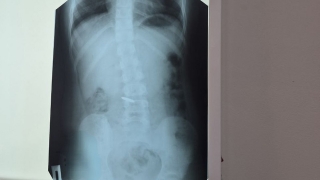

Новый выпуск программы "Школа доктора" на "TVSAR" (проект ИА "Взгляд-инфо") посвящен аппендициту.

"Статистические данные показывают, что от 20% до 40% госпитализаций пациентов с болями в животе приходятся на острый аппендицит. Типичная картина острого аппендицита начинается с болевого синдрома в верхних отделах живота или с нелокализованных болей во всех отделах брюшной полости", - говорит специалист.

"В ряде случаев клиническая картина острого аппендицита маскируется и похожа на проявление заболеваний желудочно-кишечного тракта, то есть симулирует язвенную болезнь, желчекаменную болезнь, заболевания мочевыделительной системы, почечную колику, у женщин гинекологическую патологию", - заявил хирург.